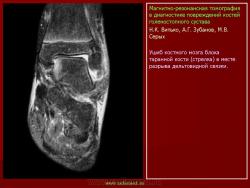

Магнитнорезонансная томография в диагностике повреждений костей голеностопного сустава.

Семиотика стресс-переломов аналогична скрытым переломам костей голеностопного сустава и стопы. Дополнительно визуализируется периостальная реакция. Однако в отличие от скрытых переломов патологические изменения визуализируются и рентгенологически.

При проведении МРТ больным с переломами костей голеностопного сустава и стопы не ставится задача оценки переломов. Изучается состояние сухожильно-связочного аппарата и параартикулярных мягких тканей. Гипсовые повязки не оказывают существенного влияния на качество и информативность изображений.